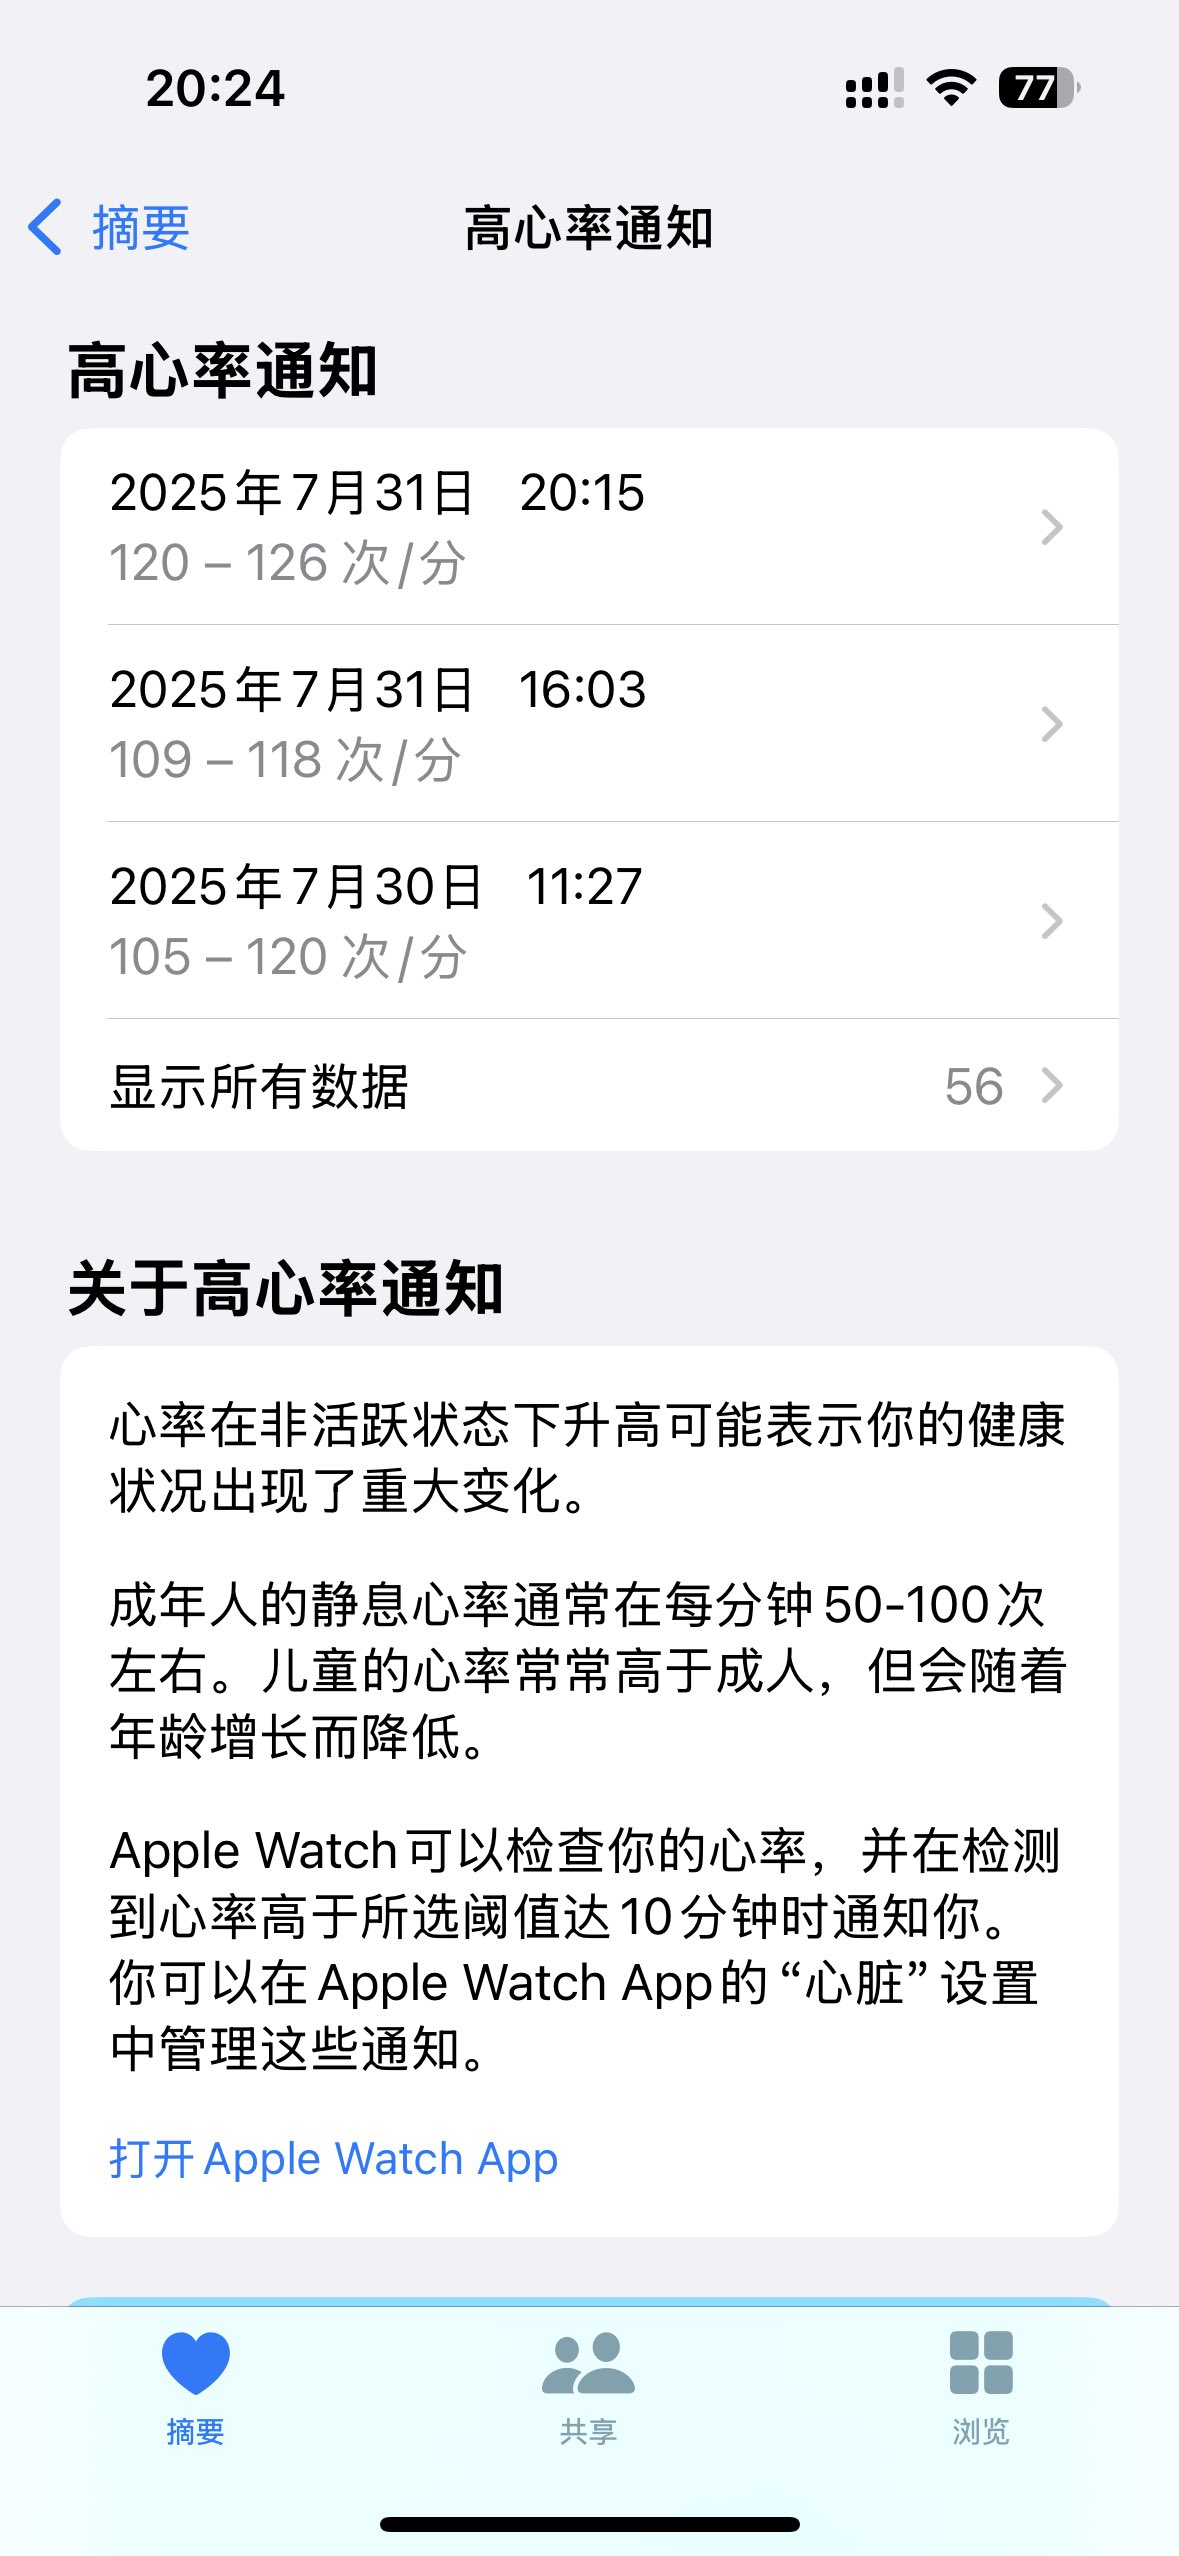

提示高心率。观察工具时手在抖,感觉呼吸还是很沉重。记忆连续性尚可。